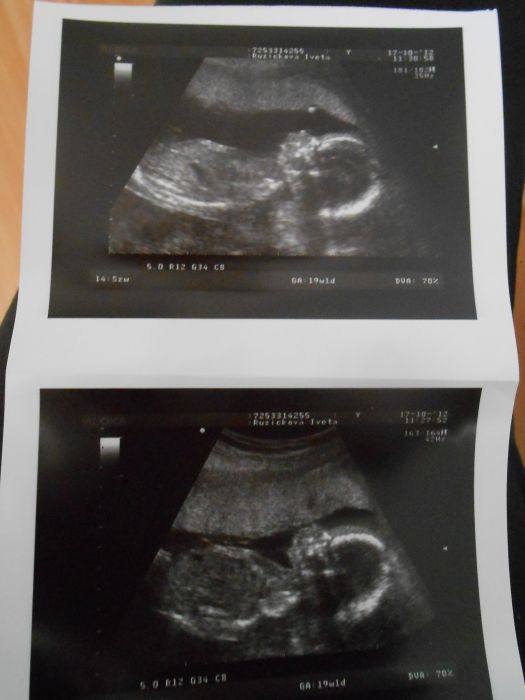

Tak hlásím příchod z UZ.Tak malý(doktor nám to potvrdil

)je v naprostém pořádku,máme vše co máme mít.Bylo to úžasné.Nejdřív říkal doktor,že si ho poměří a podívá se na něho.Přitom neříkal vůbec nic,pořád mi jezdil po břichu a sledoval.Přítel stál hned u obrazovky a vždy jak malý něco udělal se začal uculovat

Bylo to príma viděl nastavajícího taťku tak šťastného.Jednu dobu měl i slzičku v oku.No a pak to doktor hlásil sestřičce a na konec otočil obrazovku na mě a vše mi ukazoval

Malý se natáčel jak manekýn,říkali jsme ,že chce aby jsme ho pořádně viděli.Pak si začal pokopkávat nožičkou jako by do rutmu,tak to jsme se museli už smát.Pak si dal nožku přes nožku a zdálo se ,že ukázal vše co měl,dal paleček do pusinky a asi se chystal spinkat

No máme zase velký zážitek

Díky všem za podporu a jedna fotečka i pro Vás

Beru dnes jsem 20+3tt podle dnešního UZ.

Holky ten UZ je normální,měří prcka důkladně-hlavičku,stehenní kost,kontroluje bříško a orgány v něm a pak průtok krve v srdíčku a kdo chce určuje pohlaví.Ptal se nás na výsledky screeningů a to bylo vše.Určil ještě datum porodu podle naměřených hodnot.